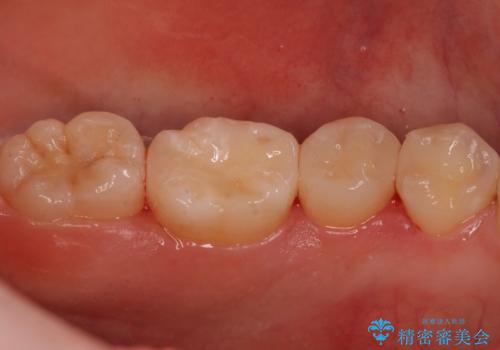

歯と歯の間の虫歯 セラミックインレーでの治療

歯と歯の間に虫歯があったため適合の良いセラミックインレーで修復処置をしていきました。

- 左下567 セラミックインレー 77,000円×3本費用は治療当時の料金となります

適合の良いインレーでの修復により再発のリスクを下げることができます。